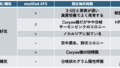

・VZV vasculopathy の診断

髄液 VZV-DNA PCRが陽性となればそれまでですが、感度が低い(最初の2週間が検出しやすい、既報では感度30%)ということが問題であり、髄液VZV-IgG index(血清IgG/髄液IgG)が有用とされています。PCRとIgGが両方陰性であれば除外できるとされています。

ちなみに鑑別疾患は、中枢神経原発血管炎(PACNS)、肉芽腫性血管炎(サルコイドーシス、梅毒、TBなど)、血栓症(トルソー、APS)、septic emboli、血管内リンパ腫などが鑑別になります(vasculopathyの鑑別)。